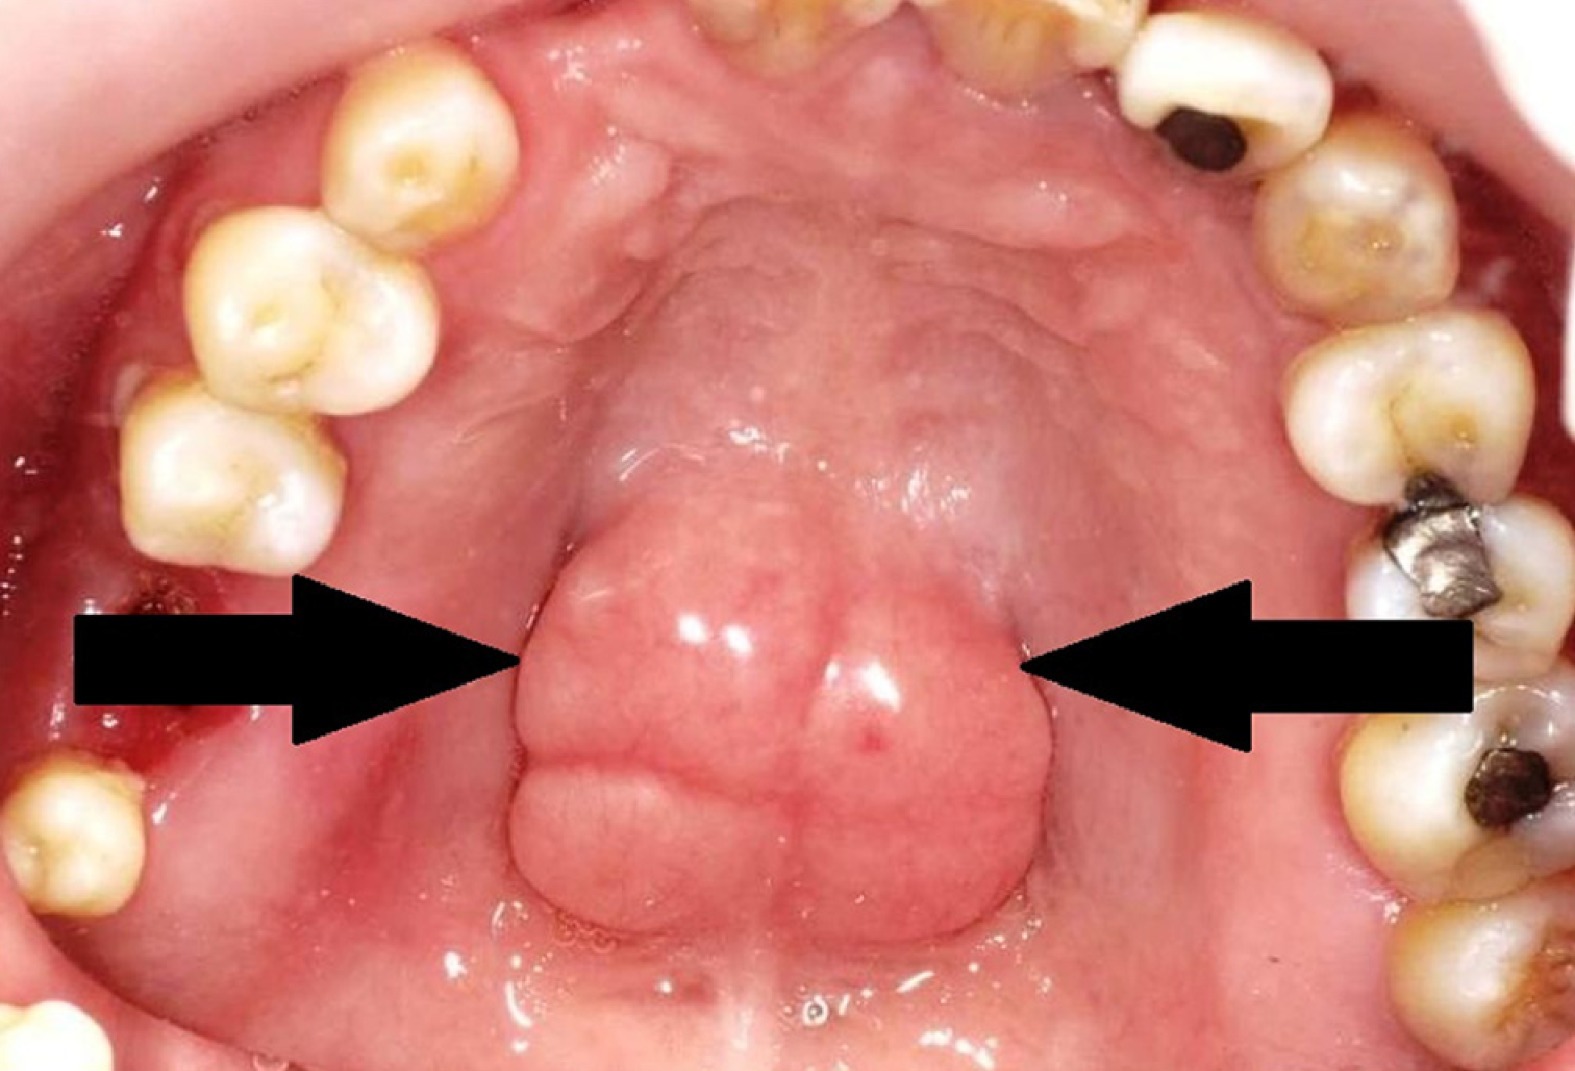

Torus palatinus is a hard bony growth that forms in the middle of the roof of the mouth (the hard palate). It grows from the jawbone and feels very firm, just like bone, because it is bone. Some people notice it early in life, while others become aware of it quite later. Many people have it and never realize it because it does not cause pain.

The shape and size of Torus Palatinus can differ from person to person. It may be: Small or large, Smooth or slightly bumpy or Flat or raised

It is always hard, fixed in place and located in the center of the palate

The skin over it is thin, which means it can sometimes get sore if injured by hard or sharp foods.